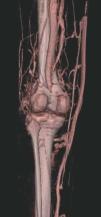

Hoy en día la utilización de los nuevos equipos TC multicorona y RM permiten la adquisición de imágenes con gran rapidez, pudiendo realizar reconstrucciones multiplanares de gran calidad, así como estudios angiográficos no invasivos13,23. Recientemente hemos estudiado 16 pacientes con síndrome de Klippel-Trenaunay mediante una venografía tomografía computarizada multicorte (TCM) o una venografía resonancia magnética tridimensional (RM-3D), utilizando imágenes axiales convencionales, reconstrucciones multiplanares (RMP), proyecciones de máxima intensidad (PMI) e imágenes tridimensionales (figs. 1-3). Las imágenes axiales convencionales fueron de utilidad para evaluar el tejido blando y el hueso y permitieron localizar el sistema venoso profundo y los vasos anómalos superficiales, determinando su relación con estructuras adyacentes. Las imágenes axiales, RMP y PMI fueron empleadas para trazar el origen, trayecto y extensión de las malformaciones venosas. Las imágenes de la superficie cutánea permitieron evaluar la localización y la extensión de la mancha en vino de Oporto y demostrar la hipertrofia de la extremidad. Las reconstrucciones tridimensionales permitieron demostrar las varicosidades y el origen y trayectoria de los vasos aberrantes (figs. 4 y 5). Ninguno de los pacientes requirió otra técnica complementaria invasiva (flebografía convencional) para confirmar el diagnóstico y planificar las estrategia terapéutica24.

Figura 4. Agenesia de la vena poplítea en paciente con síndrome de Klippel-Trenaunay.

Así, podemos concluir que una venografía TC o una venografía RM en 3D en niños y embarazadas para limitar la radiación puede ser la prueba de elección para estudiar a fondo una malformación vascular extensa localizada en una extremidad. Esta técnica permite conocer la localización exacta de la lesión en un plano tridimensional, detectando una posible infiltración musculoesquelética y extensión torácica y/o abdominopélvica, además permite valorar cambios en la densidad ósea (osteoporosis) y dismetrías, así como comprobar la existencia de sistema venoso profundo y su permeabilidad (figs. 6-9). También son de utilidad para detectar anormalidades del sistema venoso superficial, demostrar las presencia de venas aberrantes o ciáticas y determinar su extensión y vía de drenaje. Aunque estos procedimientos siguen siendo inferiores a la arteriografía o flebografía convencionales al no proporcionar el mismo grado de información sobre la hemodinámica de la malformación, representan un avance muy significativo, y en nuestra experiencia sólo será necesaria la complementación con procedimientos invasivos en casos de hipoplasias vasculares donde no esté claro el funcionamiento hemodinámico del vaso24,25.

Figura 7. La angio-tomografía axial computarizada (TAC) muestra tridimensionalmente la relación de los vasos con el tejido muscular.